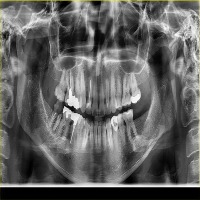

vzrad2 Computer Vision Project

Arshs Workspace Radio

downloadsClasses (93)

Amalgam filling

Bone Loss

Calculus

Caries

Cavity

Composite filling

Crown

Cyst

Implant

Periapical lesion

Root canal filling

A description for this project has not been published yet.